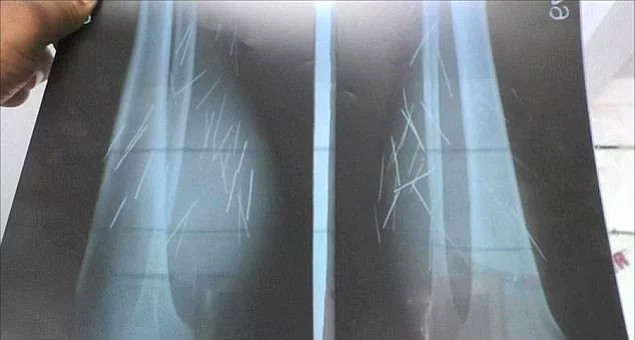

İddialarına göre 2012 yılından bu yana bacaklarında ne olduğuna anlam veremediği keskin nesneler belirmeye başladı. Doktorlar gereken araştırmaları yaptıklarında, kadının bacaklarında 70 keskin madde buldular. Bunlar arasında iğneler ve çiviler de bulunuyor.

Son beş yıldır devam eden şiddetli ağrı yüzünden artık yürümede, oturmada ve ayakta durmada zorluk çekmeye başladı. Şu an ise ağrılarına çözüm bulacak ilaçlar için doktorlara yalvarıyor.

Doktorlar Anusuiya'nın bu maddeleri bacağına kendisinin soktuğuna inanıyorlar. Ama genç kadın kendine zarar vermediğini söylemeye devam ediyor. 'Beş yıldır bu sorunu yaşıyorum. Bacaklarımda birden iğneler belirdi. Herhangi bir açıklamam yok, oraya nasıl girdiklerine dair herhangi bir fikrim yok ve sürekli var olan acıdan bıkmış durumdayım. Doktorlar bunun bir çeşit hastalık olduğunu söylüyorlar. Ama hiçbiri durumun ne olduğunu anlamış gibi durmuyor. Yalnızca birilerinin bana yardım etmesini istiyorum. Her gün acı çekiyorum, bunun artık bitmesini istiyorum.'